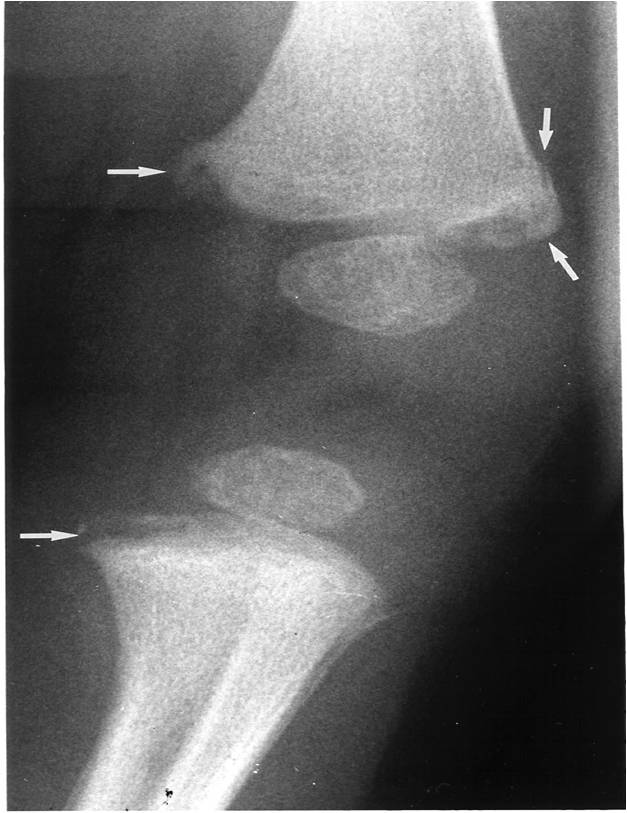

Fractura en Asa de cubo

Otra diapositiva de la fractura en Asa de cubo